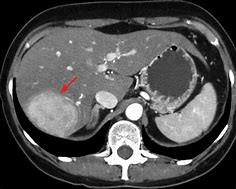

A tomografia computadorizada de abdome revela lesão bem delimitada, com hipervascularização irregular após administração de contraste. Geralmente tem aspecto heterogêneo devido à hemorragia, necrose e fibrose.